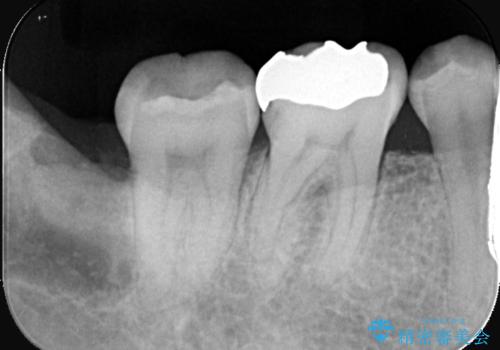

歯の根元の虫歯も精密治療で解決

- 右下6番と7番の奥歯に、歯の根元部分の虫歯(根面カリエス)を認め来院されました。通常の虫歯よりも進行しやすい根面カリエスは、再発リスクを抑えた治療が重要です。患者様のご希望と口腔内の状態を考慮し、虫歯を徹底的に除去し、精密で耐久性の高いセラミッククラウンで修復する治療計画を立案しました。これにより、長期的な再発防止と咬み合わせの機能回復を目指します。

治療ではまず、感染した歯質をマイクロスコープで確認しながら慎重に除去。その後、セラミッククラウンを装着するための歯の形成を行いました。型取りから患者様の歯の形や色に合わせたオーダーメイドのセラミッククラウンを作製。セラミックは、プラークが付着しにくく、再治療のリスクを低減する特性があります。最終的に、精度の高いクラウンを装着し、咬み合わせを細かく調整しました。これにより、根面カリエスが再発しにくい環境を整え、快適に食事ができる奥歯を取り戻していただけました。